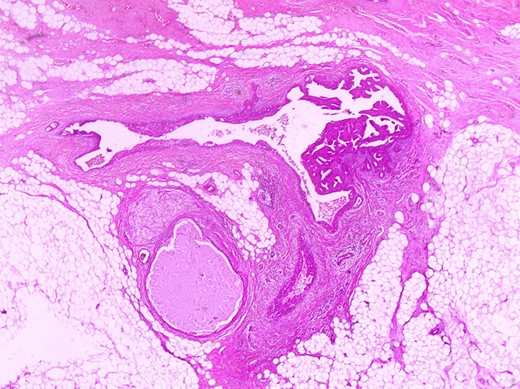

The histologic examination revealed an intraductal papilloma of 9 mm in maximum diameter with no evidence of atypia or malignancy (Figs 3,4 and 5).

The same duct with the papillary projections. The wall is fibrotic and there are also foci of usual type of epithelial hyperplasia (H+E×100).